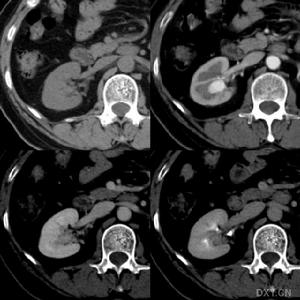

糖尿病性腎病變一般資料

1996年~1999年一共收集符合DM性腎病變患者108例,隨機分為黃芪注射液治療組72例和補中益氣湯對照組36例。其中男性63例,女性45例,年齡38~82歲,平均57.2±11.4歲,病程3~32年,平均8.31±4.15年,症狀、體徵為蛋白尿(100%)、高血壓(89%)、雙下肢浮腫(82%)、氮質血症(Scr178~442umol/L)47例,尿毒症(Scr>442umol/L)9例,頭暈昏沉(100%)、神疲倦怠(99%)、心悸氣短(86%)、腹脹納呆(42%)、腰膝酸軟(62%)、舌苔滑膩(59%)、脈沉(81%)、弦(52%)、滑(87%)、細(50%),經χ2檢驗,兩組間性別、年齡、病程、體徵、症狀等均無顯著性差異(P>0.05)。